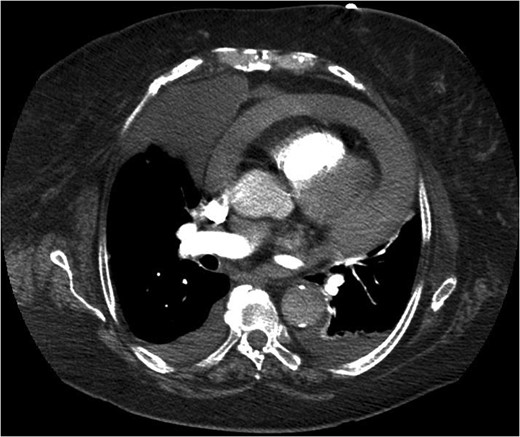

She represented later to our unit with recurrent vomiting. Her investigations revealed a raised lactate and acidosis on arterial blood gas. There was a concern for gastric ischaemia; the decision was taken to proceed to theatre. Given that she was haemodynamically stable with no peritonitis, we chose to operate using a laparoscopic approach. Surgery was performed through four laparoscopy (2Â Ă—Â 11 mm, 2Â Ă—Â 5 mm). A diagnosis of Morgagni hernia was made (Fig. 2). Inside the hernial sac was the transverse colon, the greater curvature of the stomach with a partial gastric volvulus (Fig. 3). The hernia was reduced with the viscera still viable but the sac could not be excised. The defect was repaired with a 6Â Ă—Â 10 cm composite mesh with an absorbable tic fixation on the diaphragm (Fig. 4). No drain was inserted, and the operation time in total was 45 minutes.